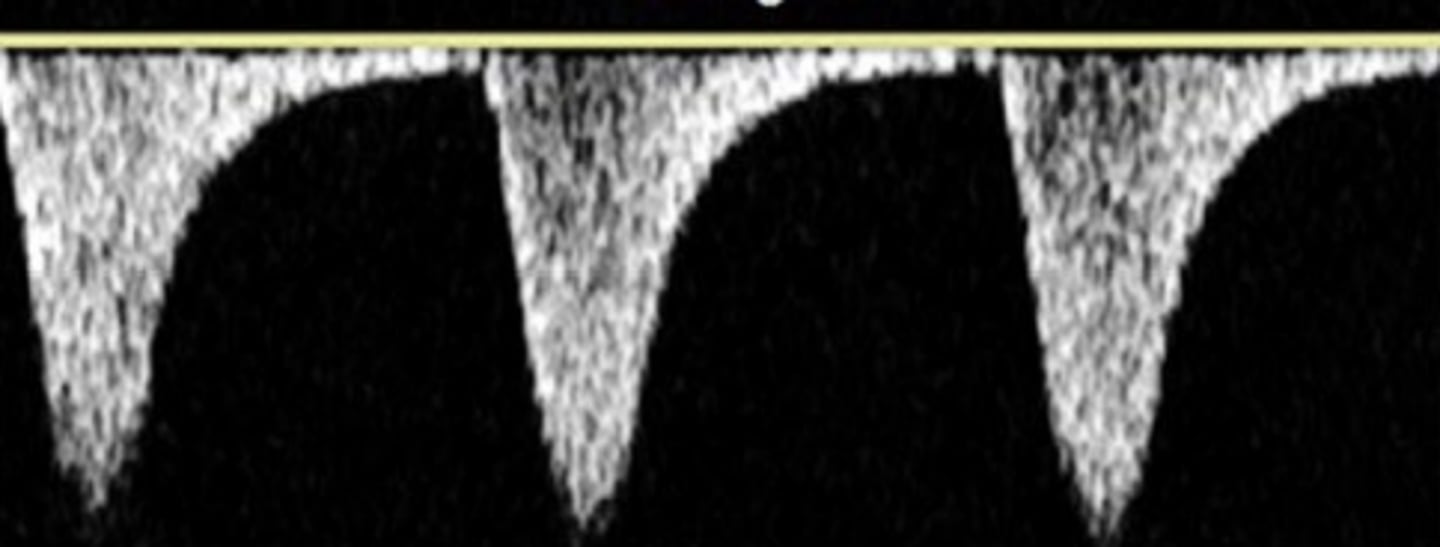

High Resistance

sharp upstroke/brisk downstroke